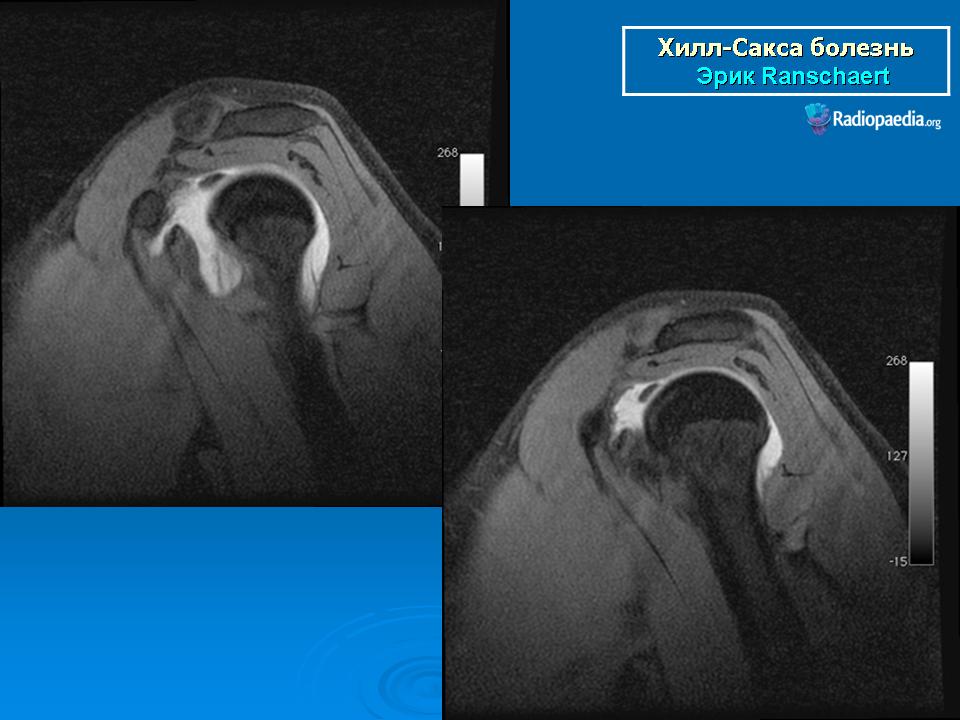

На рентгенограмме плечевого сустава определяется умеренный остеопороз головки плечевой кости. Иногда на ее задненаружной поверхности позади вершины большого бугорка выявляется вдавленный дефект (повреждение Хилл-Сакса). Дефект четко виден на рентгенограмме в аксиальной проекции. Аналогичный, но менее выраженный дефект может быть выявлен в зоне передненаружного края суставной впадины лопатки. Также в диагностике причин привычного вывиха плеча помогает МРТ исследование.